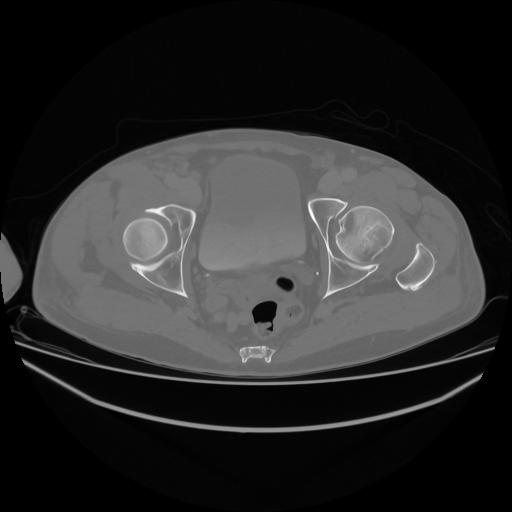

5 CUERPO,CE,Vol,1.0,CUERPO,,